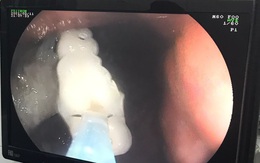

Bị ho khi đang ngủ, người đàn ông bất ngờ nuốt 4 răng giả vào phế quản

TTO - Ngày 24-5, các bác sĩ nội soi Bệnh viện Đa khoa trung ương Cần Thơ vừa thực hiện nội soi can thiệp lấy hàm răng giả 4 chiếc, bị kẹt trong phế quản một nam bệnh nhân.